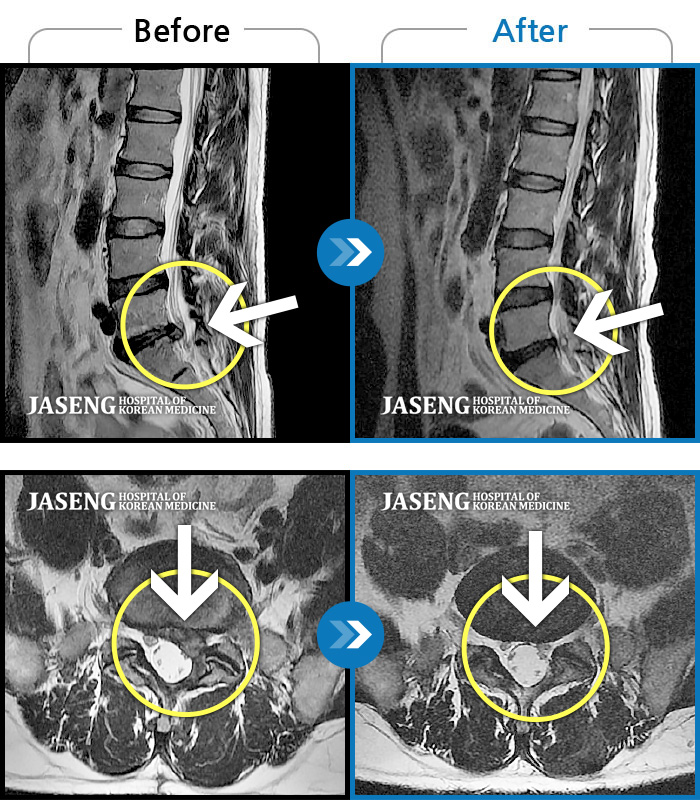

허리, 좌측 골반부터 좌측 다리로 통증 및 저림이 지속되고 좌측 다리의 감각이 둔함

촬영시기

2024.09.30 ~ 2025.11.25

2025.12.05